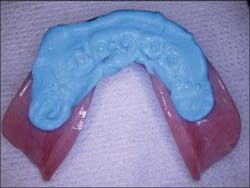

Figure 2 - Interim denture ready to be converted to fixed provisional restoration

Figure 8 - The antaglio surface of the prosthesis depicting the imprinted surface of the multiunit abutments on the polyvinyl material

Figure 9 - Preparation of the prosthesis to pick up the temporary cylinders and convert the interim denture into the fixed provisional restoration

The mandibular prosthesis was aligned with the maxillary prosthesis intraorally using the previously recorded bite registration. Polyvinyl siloxane material was placed on the antaglio surface of the mandibular denture. The patient was guided into centric relation, thus capturing the imprinted location of the multiunit abutments onto the polyvinyl siloxane material (Figure 8). The prosthesis was then removed and holes were drilled corresponding to the location of the abutments (Figure 9).